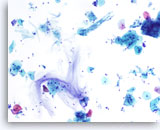

Lubricant D treated vial

…showing evidence of the lubricant present as a semi solid matrix resembling thin mucous. The lubricant stains a purplish hue in the background and is loosely associated with the epithelial cells. The cellularity is decreased as compared to the control. The lubricant effect in this case may not be as obvious to the observer.

10x

Lubricant D treated vial

…showing evidence of the lubricant present as a semi solid matrix resembling thin mucous. The lubricant stains a purplish hue in the background and is loosely associated with the epithelial cells. The cellularity is decreased as compared to the control. The lubricant effect in this case may not be as obvious to the observer.

10x